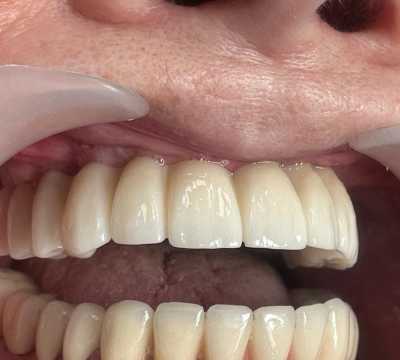

S-au inserat 10 implanturi dentare la nivel maxilar si 7 la nivel mandibular, pe baza carora s-au realizat protezari fixe metalo-cermice mandibular si ceramica pe zirconiu la nivel maxilar.

N.B. Cel de-al 7-lea implant mandibular a fost inserat la o luna distanta de la interventia initiala- defectul osos local fiind prea avansat pentru inserarea implantului in acelasi timp operator.